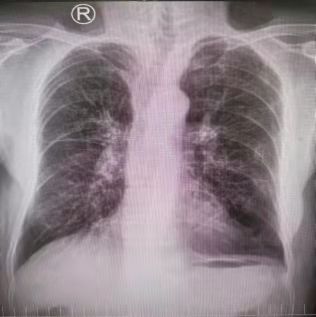

患者,男,77歲,氣短、咳嗽,慢阻肺、高血壓病史多年。肺功能?chē)?yán)重受損,稍活動(dòng)即感呼吸困難。因聲音嘶啞就診我市知名三甲醫(yī)院,診斷“聲帶腫物”,因重度肺功能損害不能耐受手術(shù)麻醉。為求確診慕名前來(lái)我院耳鼻喉科就診。經(jīng)頸部CT檢查提示:“右側(cè)聲帶新生物”。不論其良、惡性腫瘤,手術(shù)切除是根除手段。

在充分評(píng)估支氣管鏡檢查風(fēng)險(xiǎn)后,首先在局麻下行電子支氣管鏡檢查:右側(cè)聲帶前中1/3可見(jiàn)腫瘤組織致喉狹窄。活檢組織病理證實(shí)為“高分化鱗癌”。因家屬有強(qiáng)烈的治療愿望,孫主任組織全科再次評(píng)估麻醉手術(shù)風(fēng)險(xiǎn)。患者重點(diǎn)、難點(diǎn)在于高齡,術(shù)中麻醉風(fēng)險(xiǎn)高,容易出現(xiàn)麻醉意外事件,難以耐受聲帶腫瘤切除并重建手術(shù)。隨后及時(shí)

組織呼吸與危重癥醫(yī)學(xué)科、耳鼻喉科、麻醉科進(jìn)行多學(xué)科討論:患者多年慢阻肺病史,肺功能極重度減退,伴有呼吸衰竭,術(shù)中可能出現(xiàn)肺通氣不良、術(shù)中出血以及手術(shù)時(shí)間較長(zhǎng)等情況均可加重呼吸衰竭,極易導(dǎo)致突發(fā)意外情況如心跳呼吸驟停等。鑒于以上各種并發(fā)癥,需要采取快速、準(zhǔn)確、高效的手術(shù)方式切除病變組織,給后續(xù)治療帶來(lái)